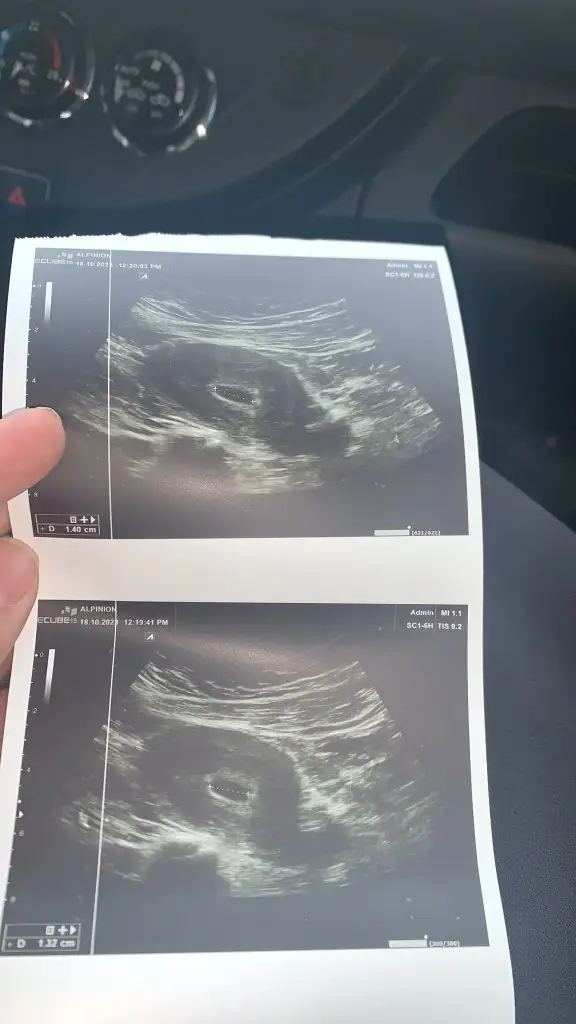

Canım 5. hafta karından keseyi ancak görürler. benim ilk gebeliğimde de 5+5 te keseyi görmüştük karından. ikinci gebeliğimden vajinal 6. haftada kese+yolk görmüştü.Kızlar beşinci hafta ultrasyon görüntüsüne bakar mısınız karından baktı bişey demedi haftaya gel kalp atışına bakalım dedi ama sizin dediğiniz yolk falan var mı yok mu bişey demedi ya

5+4 dü dün işte karından baktı yolk falan bişey demedi haftaya gelirsin kalp atışı için dedi bende bi an boş gebelik mi diye korktum yaCanım 5. hafta karından keseyi ancak görürler. benim ilk gebeliğimde de 5+5 te keseyi görmüştük karından. ikinci gebeliğimden vajinal 6. haftada kese+yolk görmüştü.

5 +1 benımde sizin gibi kese gordu bısey demedi ikinci gittigimde 6+2 de kalp duyduk endişe etmeyin ufak oldugu için gözükmüyor demişti5+4 dü dün işte karından baktı yolk falan bişey demedi haftaya gelirsin kalp atışı için dedi bende bi an boş gebelik mi diye korktum ya